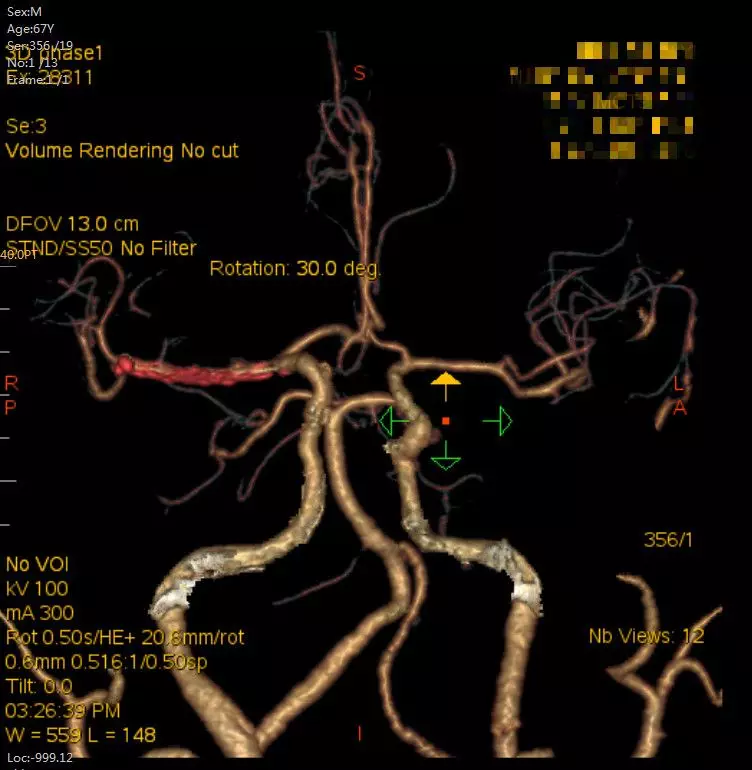

术后头颈部CTA(08-07日 17:23分)